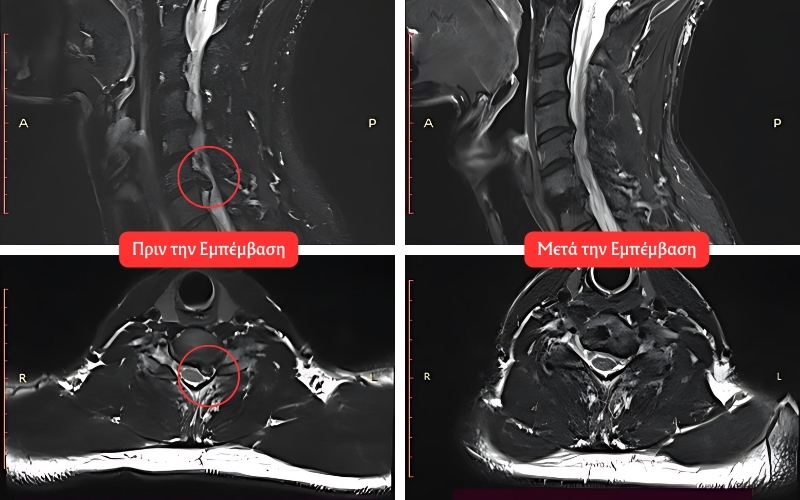

Η ενδοσκοπική δισκεκτομή είναι μία τεχνική κατά την οποία αφαιρείται το προεξέχον ή ραγισμένο τμήμα ενός μεσοσπονδύλιου δίσκου που πιέζει τα νεύρα και προκαλεί πόνο. Η διαδικασία πραγματοποιείται μέσω μικρών τομών και χρησιμοποιεί το ενδοσκόπιο, έναν λεπτό σωλήνα με κάμερα και πηγή φωτός, που επιτρέπει στον χειρουργό να βλέπει και να διορθώνει βλάβες μέσα στη σπονδυλική στήλη με μεγάλη ακρίβεια.

3. Αφαίρεση της Δισκοκήλης: Χρησιμοποιώντας ειδικά ενδοσκοπικά εργαλεία, ο χειρουργός αφαιρεί το προεξέχον ή ραγισμένο τμήμα του δίσκου που προκαλεί πίεση στα νεύρα.